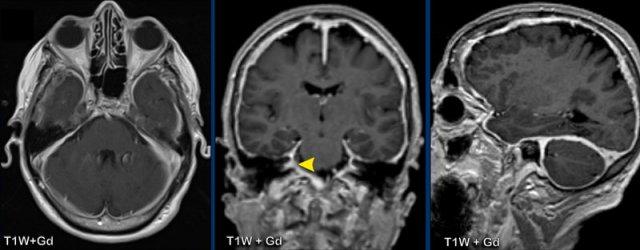

Đây là một ca bệnh tương tự của bệnh nhân có triệu chứng đau đầu và mất thính lực hai bên.

Hình ảnh

Có dày màng cứng kèm ngấm thuốc với hình thái hơi không đều.

Không có ứ máu tĩnh mạch.

Sự ngấm thuốc lan vào ống tai trong (đầu mũi tên vàng).

Tiếp tục với các hình ảnh sau điều trị…

Cùng bệnh nhân trước và 6 tháng sau điều trị steroid với sự thoái lui hoàn toàn các bất thường.